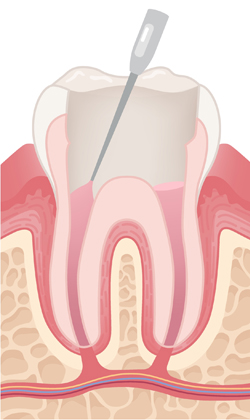

A tooth that has had a root canal treatment is not as sturdy as before, due to the removal of a large portion of the pulp. Thus it is common that the root canal treatment is followed by restorative procedures to place a post, core and crown.

The treated tooth is sealed with new crown.